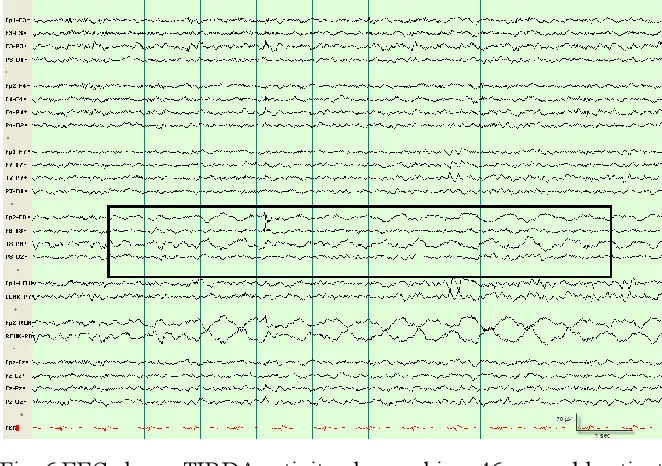

要了解医生在比较脑癌患者和健康人的神经活动时会注意什么,请看这些图片。

脑电图显示在一名 46 岁的胶质母细胞瘤患者身上观察到的颞叶间歇性有节律的 delta 活动,高亮区域显示异常的 delta 节律。